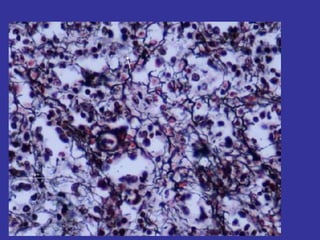

CELULAS CEBADAS

MASTOCITOS. Celulas cebadas

Se localizan el tejido conjuntivo, a lo largo

de los vasos sanguíneos.

Debajo del epitelio de los sistemas

respiratorio y digestivo .

FUNCION Procesos inflamatorios ,

Hipersenbilidad reacciones alérgicas .

Fijas

CELULAS

CEBADAS

1- origen de las células

mesenquimatosas

indiferenciadas.

2-forma ovalada, núcleo

esférico de posición central

o excéntrico

3- Citoplasma lleno de

gránulos esféricos basófilos

( histamina)